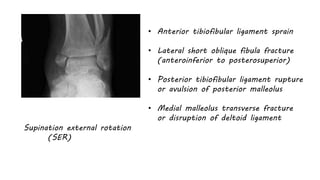

Supination external rotation

(SER)

• Anterior tibiofibular ligament sprain

• Lateral short oblique fibula fracture

(anteroinferior to posterosuperior)

• Posterior tibiofibular ligament rupture

or avulsion of posterior malleolus

• Medial malleolus transverse fracture

or disruption of deltoid ligament

Supination external rotation (SER) •Anterior tibiofibular ligament sprain • Lateral short oblique fibula fracture (anteroinferior to posterosuperior) • Posterior tibiofibular ligament rupture or avulsion of posterior malleolus • Medial malleolus transverse fracture or disruption of deltoid ligament